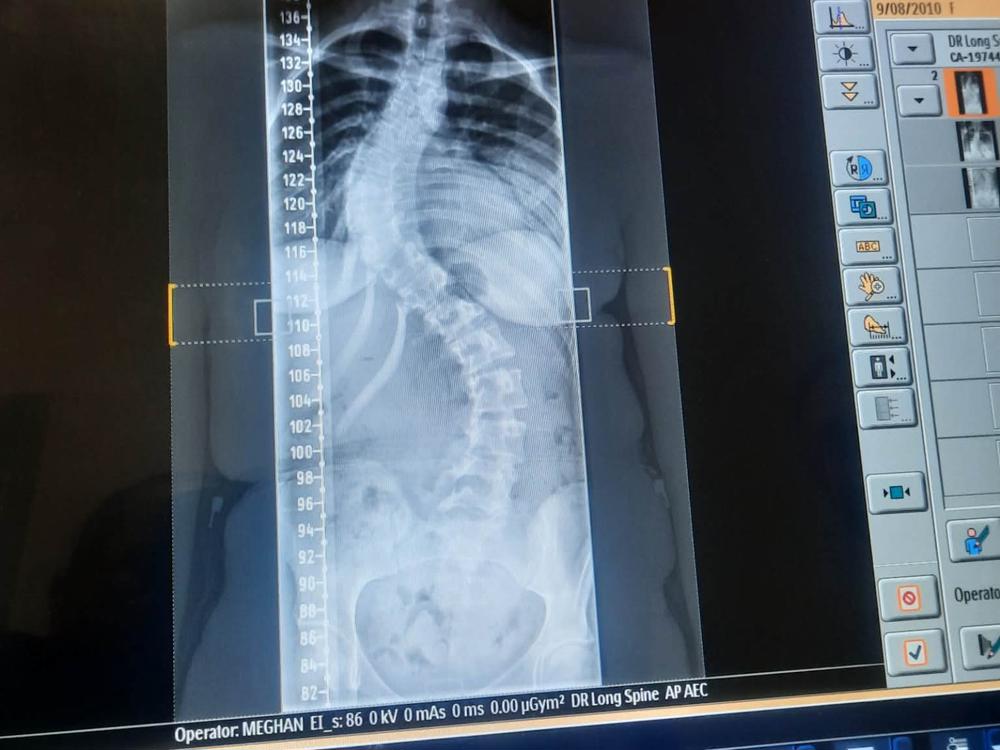

Sammi... my daughter has just been diagnosed with Scoliosis.

She is 15 years old, and is the kindest, most caring little girl you could know. She does not deserve this. Please help my wee princess, this is breaking my heart.